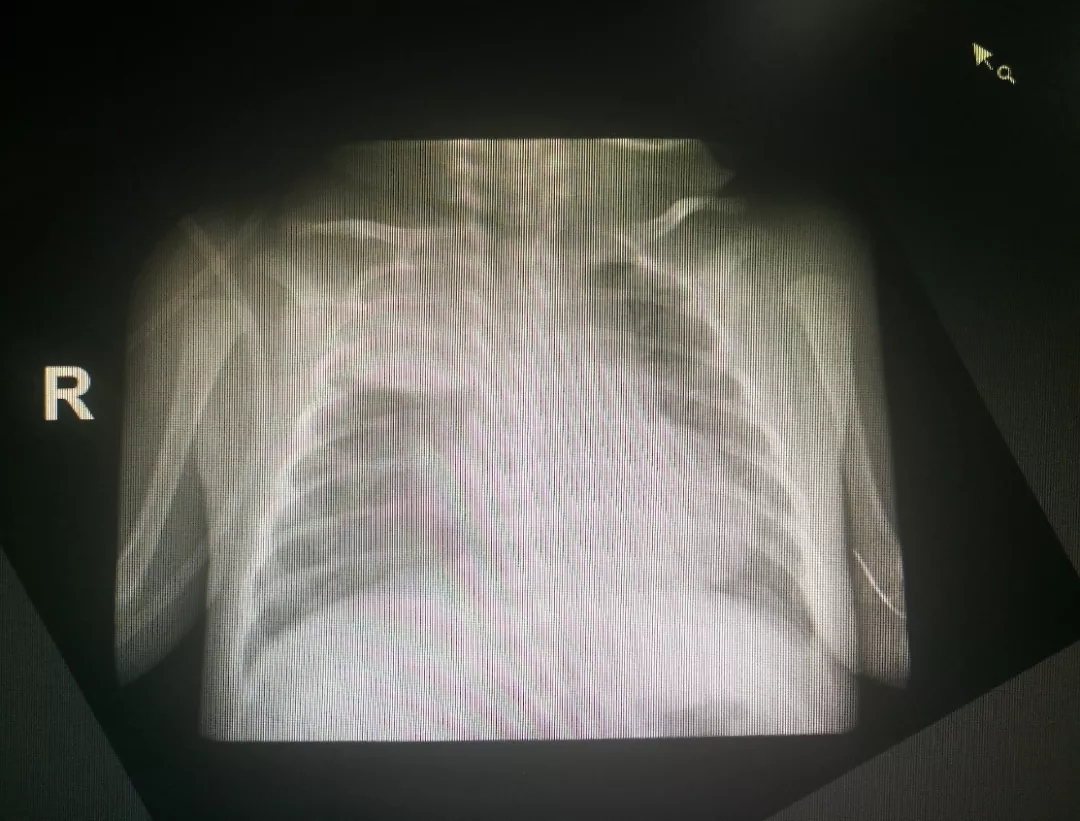

术前胸片

患儿“胎龄33周+2天,出生体重1.37Kg”,经过医护人员的精心治疗后,体重增长至2Kg,但该患儿因右上肺肺不张继发呼吸衰竭,经过呼吸机等一系列治疗措施未见症状好转。新生儿科韦彦成主任、石景喆副主任与儿内科支气管镜技术团队共同研究病历,取得患儿家属的同意和配合后,决定给患儿进行电子支气管镜检查+肺泡灌洗术。

在新生儿科医护团队的悉心治疗及护理下,患儿病情稳定,逐渐予撤除有创呼吸机改为经鼻高流量给氧支持治疗,复查胸片提示右肺不张明显好转,治疗效果显著。现患儿处于康复阶段。该患儿成功实行电子支气管镜灌洗治疗,标志着我院新生儿支气管镜诊疗技术又上了一个新的台阶。